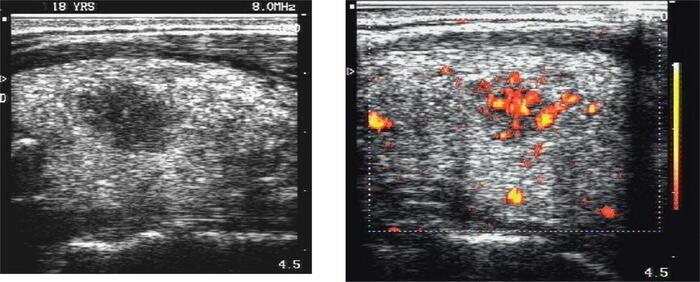

- Đặc điểm nghi ngờ ác tính: Viền mờ, có vi vôi hóa, chiều cao lớn hơn chiều rộng, tăng sinh mạch máu bất thường bên trong nhân.

Bước 4: Đánh giá nhân tuyến giáp (thyroid nodules)

Xác định: vị trí, kích thước, ranh giới (rõ hay mờ), dạng đặc hay nang, thành phần hỗn hợp, mức độ đồng nhất, và có hay không các dấu hiệu nghi ngờ ác tính như:

- Vôi hóa vi thể (microcalcification)

- Bờ không đều

- Hình dạng cao hơn rộng (“taller-than-wide”)

- Tăng sinh mạch bất thường khi siêu âm Doppler